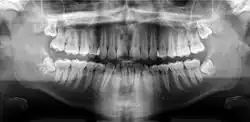

A dental panoramic radiograph, showing the maxilla and mandible, all the teeth including the "wisdom teeth," the frontal and maxillary sinuses, the nasal cavity and the temporomandibular joint and other near by head and neck anatomy.